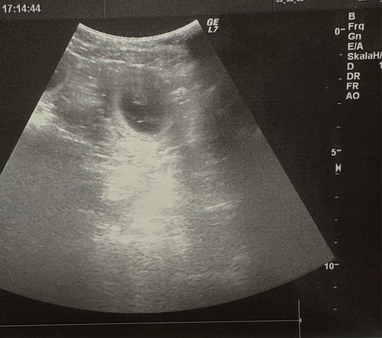

12.01.2026

Hanni ist laut Ultraschalluntersuchung tragend - wir erwarten die Welpen um den 18.02.2026